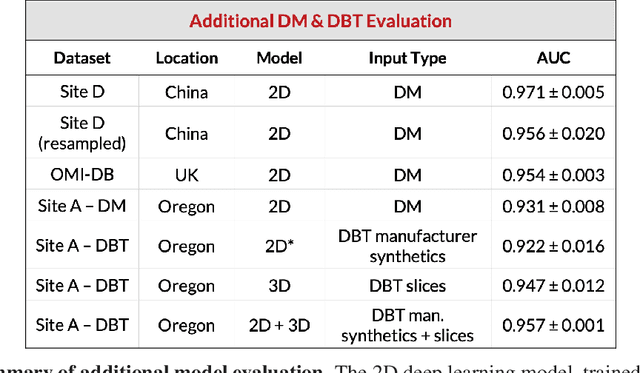

Robust breast cancer detection in mammography and digital breast tomosynthesis using annotation-efficient deep learning approach

Dec 27, 2019

Breast cancer remains a global challenge, causing over 1 million deaths globally in 2018. To achieve earlier breast cancer detection, screening x-ray mammography is recommended by health organizations worldwide and has been estimated to decrease breast cancer mortality by 20-40%. Nevertheless, significant false positive and false negative rates, as well as high interpretation costs, leave opportunities for improving quality and access. To address these limitations, there has been much recent interest in applying deep learning to mammography; however, obtaining large amounts of annotated data poses a challenge for training deep learning models for this purpose, as does ensuring generalization beyond the populations represented in the training dataset. Here, we present an annotation-efficient deep learning approach that 1) achieves state-of-the-art performance in mammogram classification, 2) successfully extends to digital breast tomosynthesis (DBT; "3D mammography"), 3) detects cancers in clinically-negative prior mammograms of cancer patients, 4) generalizes well to a population with low screening rates, and 5) outperforms five-out-of-five full-time breast imaging specialists by improving absolute sensitivity by an average of 14%. Our results demonstrate promise towards software that can improve the accuracy of and access to screening mammography worldwide.